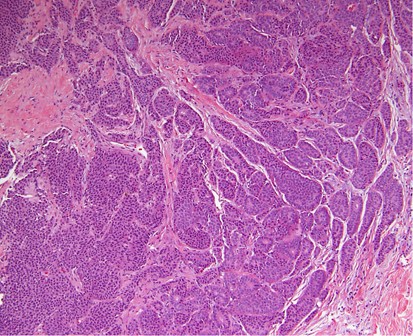

Glass slides were available for review in 53 out of 85 (62%) cases. These slides included 28 core biopsies and 30 excisions (5 cases with both cores and excisions). Seven cases involved lymph nodes only (6 axillary and 1 intramammary). The remaining 46 cases all involved the breast. Mammary lymphatic only involvement, without stromal invasion, occurred in 7% (3/46) of the cases. Certain recurrent histological features were identified, including a well-circumscribed nodule (74%, 34/46), often surrounded by a fibrous pseudocapsule (52%, 24/46) with varying thickness (Figure 1) and absence of an in situ mammary carcinoma. Interestingly, in the great majority of the tumors, lymphovascular invasion was notably absent (87%, 40/46). Tumoral calcifications were observed in non-mammary metastases of serous carcinoma type that were psammomatous in nature (75%, 6/8) (Figure 2), including two cases that involved lymph nodes.

High-grade ovarian serous carcinoma metastatic to the breast. The tumor has overlapping morphologic features with primary breast cancer with medullary or atypical medullary features including a solid growth pattern, central necrosis, a host inflammatory response and marked cytologic atypia. Ovarian high-grade serous carcinoma was the most commonly misdiagnosed tumor in this series.